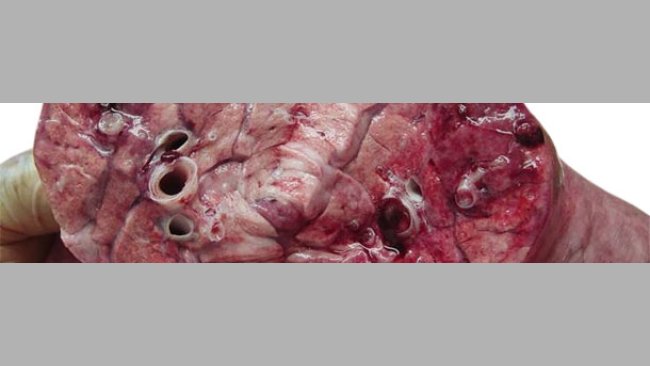

Caso clinico: Polmonite necrotizzante in suinetti lattanti

In un allevamento di moltiplicazione del Messico si osserva un aumento della mortalità in sala parto coincidendo con un aumento della temperatura ed umidità ambientale.